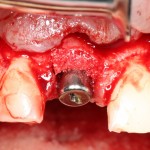

После удаления зуба и сопутствующей гранулемы, остается большая по размеру лунка с тонкой и поврежденной воспалительным процессом вестибулярной стенкой:

Первым делом, необходимо определиться с подготовкой лунки под имплантат. Проверить правильность позиционирования лунки можно с помощью аналогов имплантов, входящих в комплект XiVE Dentsply Implants:

Напомню, что при правильном позиционировании импланта в области фронтальных зубов, он прилегает к небной стенке лунки, а его ось выходит на небную поверхность будущей коронки. В крайнем случае, на режущий край.

Имплантат по объему всегда меньше, чем сам зуб:

Поэтому у нас возникает вопрос заполнения «пустого» пространства между вестибулярной стенкой лунки и поверхностью импланта. И, как ни странно, с Bio-Oss Collagen это удобнее сделать до установки имплантата.

Графт адаптируется (с помощью скальпеля), устанавливается в нужное положение. Для этого, опять же, очень удобно использовать аналоги имплантов из имплантологического набора (в крайнем случае, остеотомы или пины параллельности):